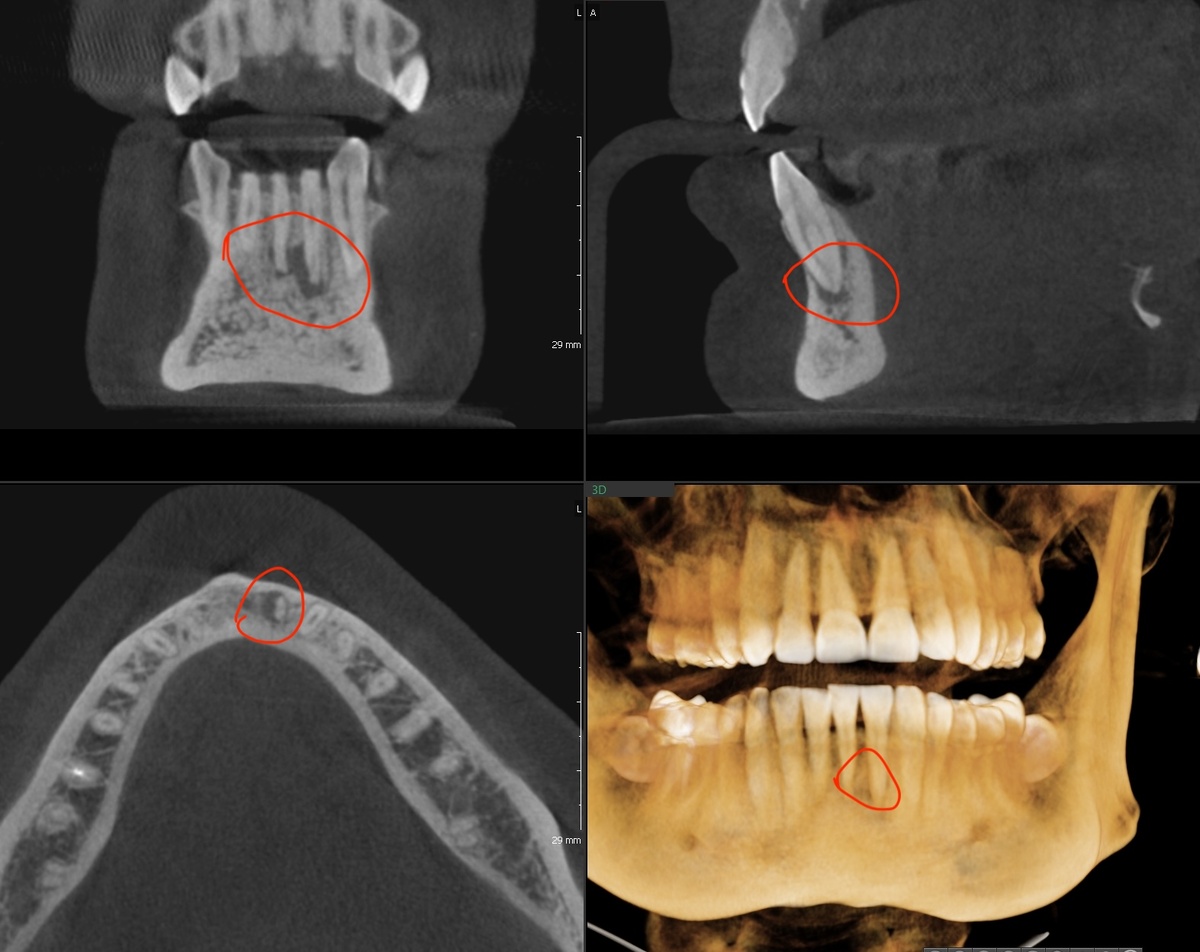

Вот как выглядел зуб в 2023 году:

2023 год

Небольшой очаг остался, остались, кстати, и ощущения в зубе, отличающие его от остальных (нормальных) зубов. На десне шрам (фиброз) - нечто инородное, выпирающее. Возможно, дело в нём. А, возможно, в мелком очаге на апексе.

Посмотрим в динамике, год 2024:

2024 год

Вроде, значительных изменений нет - ни в хорошую сторону, ни в плохую. Канал расширили знатно, не уверена, то зубу на пользу пойдёт повторная эндодонтия. Пускай остаётся в таком виде, в каком он есть сейчас.

Станет хуже - буду думать. Всегда есть РВК в закромах (резекция верхушки корня).